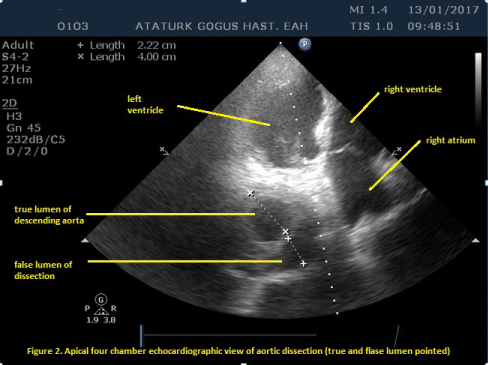

An elderly man aged 82 years who had hypertension for 22 years was admitted to the emergency department with severe chest and back pain. According to information gained from the patient, he has used regularly hypertension medical (perindopril + indapamide 4/1.25 mg) and he had no history of other chronic disease (cardiac disease, kidney disease, diabetes mellitus or connective tissue disorder), operations, or hospitalization. When he arrived at the hospital, his blood pressure was 140/70 mmHg, heart beat was 72 beats per minute, electrocardiography was normal, and D-dimer was high (1390 ng/mL). The patient was referred to our hospital with a diagnosis of pulmonary embolism. Transthorasic echocardiography (TTE) showed that the diameter of ascending aorta was nearly 10.3 cm (Figure 1) and, in the apical four chamber view decending aorta had dissection with true and false lumen (Figure 2). TTE revealed that his ejection fraction was 60% (used modified Simpson calculation), and there was minimal regurgitation of the aortic valve. Thoracal computed tomography angiography (CTA) showed type B aortic dissection (Figure 3). There was a aortic aneurysm that started from aortic valve and including the ascending aorta and there was a aortic dissection with clearly visible true and false lumen on the decending aorta. The diameter of ascending aorta was 92.9 mm on CTA. IV esmolol and sodium nitroprussid infusion was initiated and the patient was consulted with cardiovascular surgeon. Due to unwillingness of the patient’s relatives and no malperfusion, thoracic endovascular aortic repair (TEVAR) or any surgical procedure was not performed.

Figure 2: Apical four chamber echocardiographic view of aortic dissection (true and false lumen pointed). View Figure 2